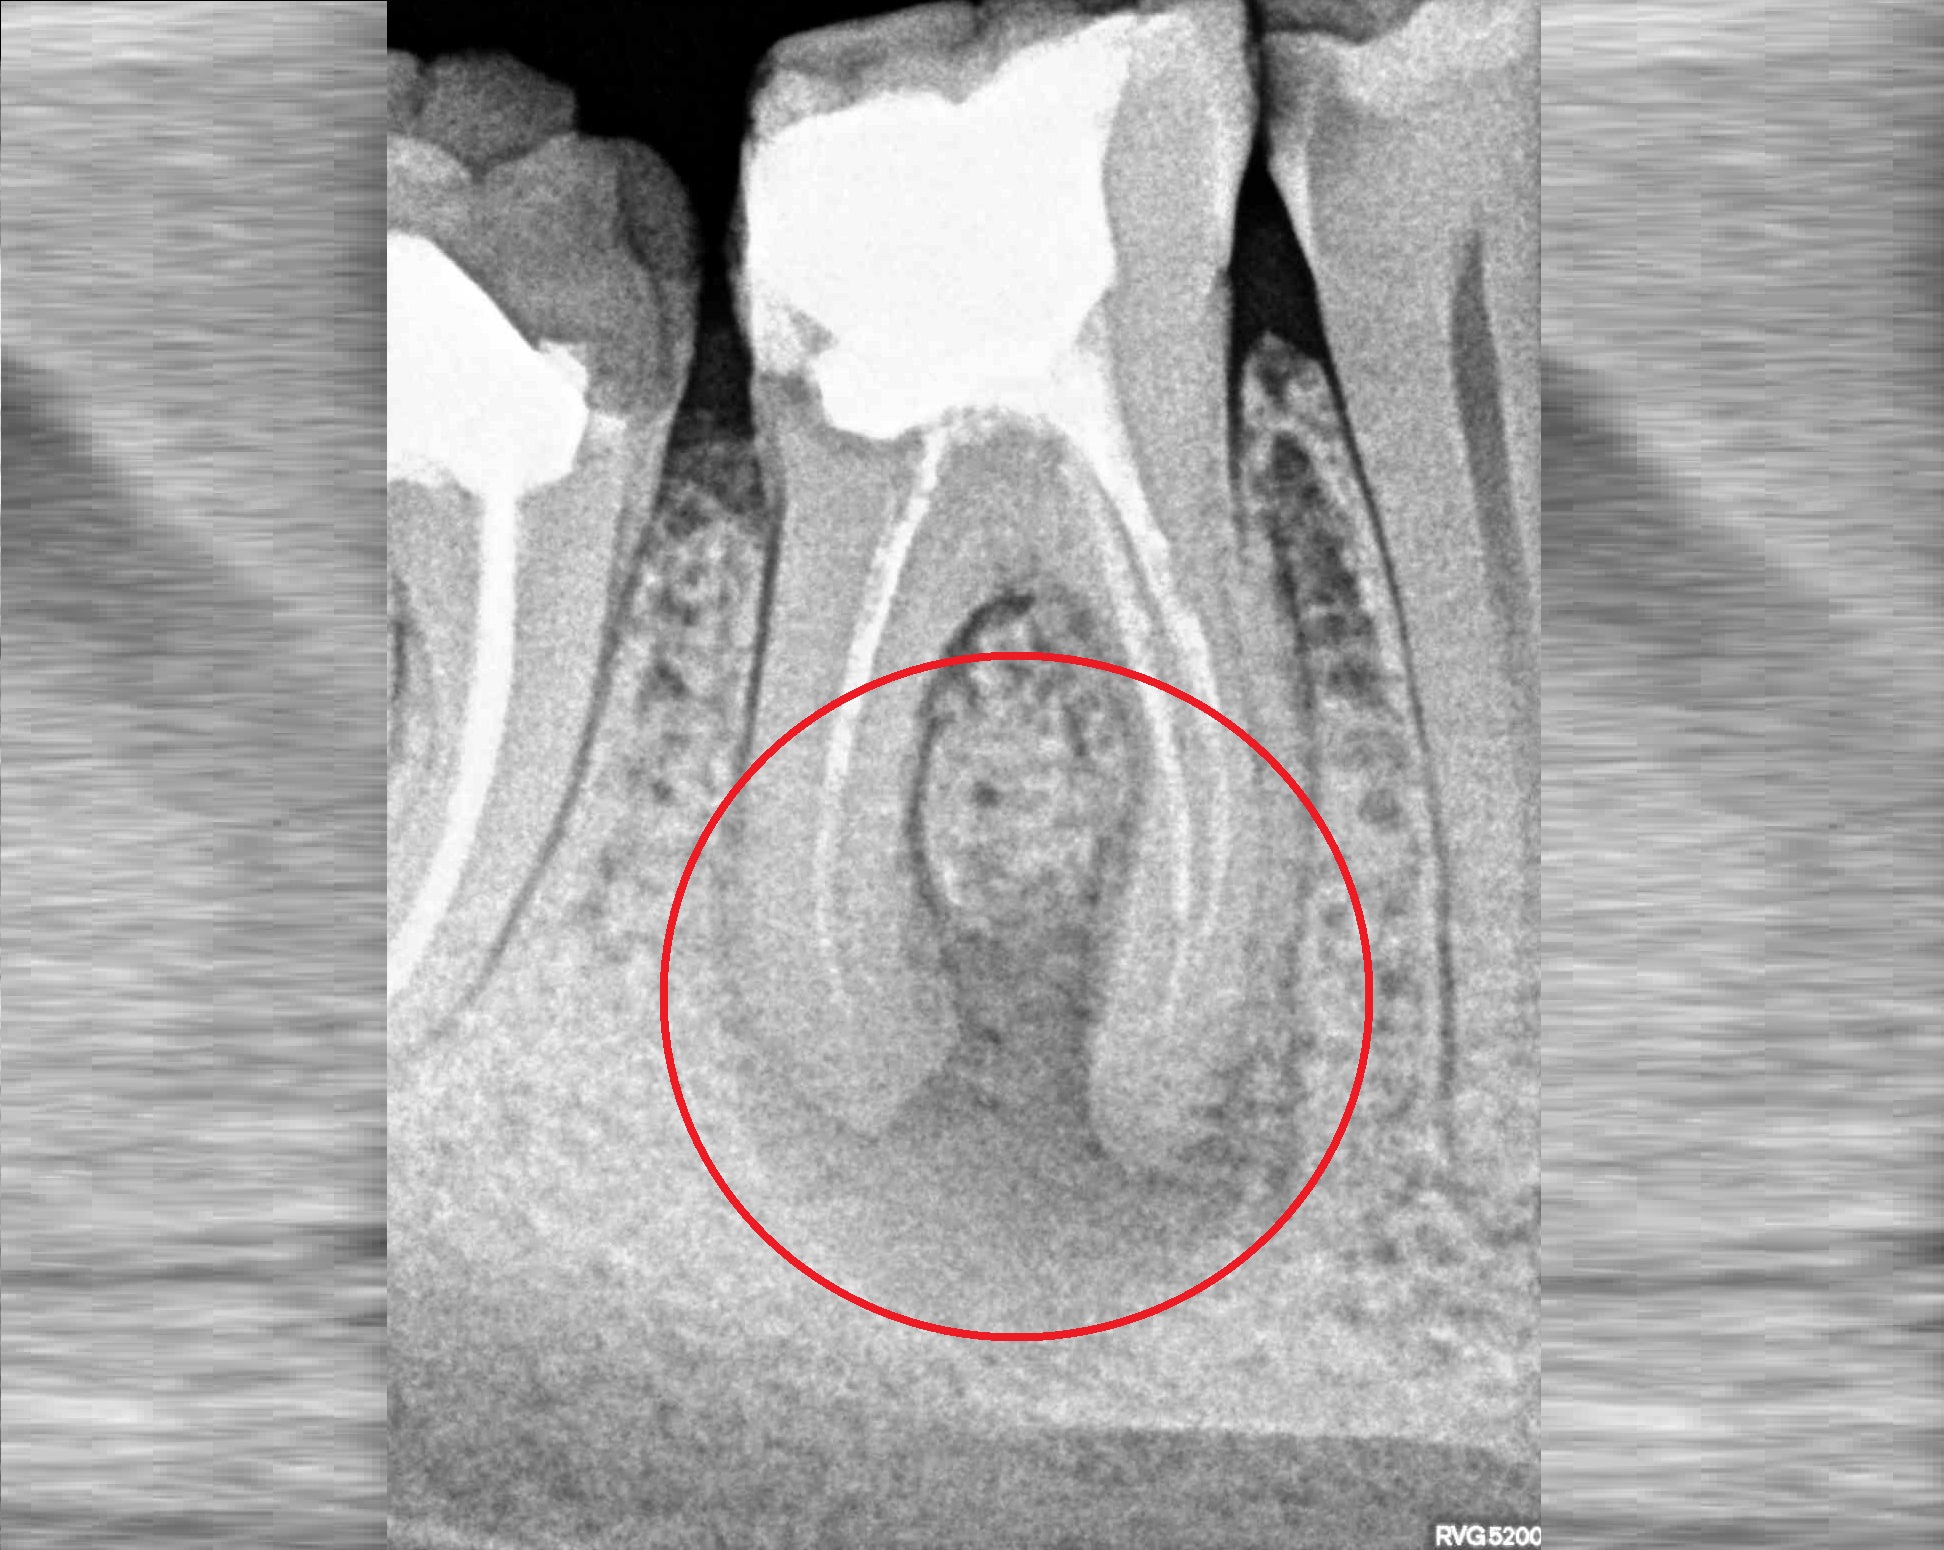

Проблема

Пациент обратился в клинику с постоянными ноющими самопроизвольными болями в зубе, усиливающиеся при накусывании, отечность тканей в области причинного зуба. После детального обследования были обнаружены значительные очаги воспаления на корнях зуба.

Решение

Пациенту было проведено эндодонтическое лечение данного зуба. В результате лечения наблюдаем восстановление костной ткани, окружающей зуб.